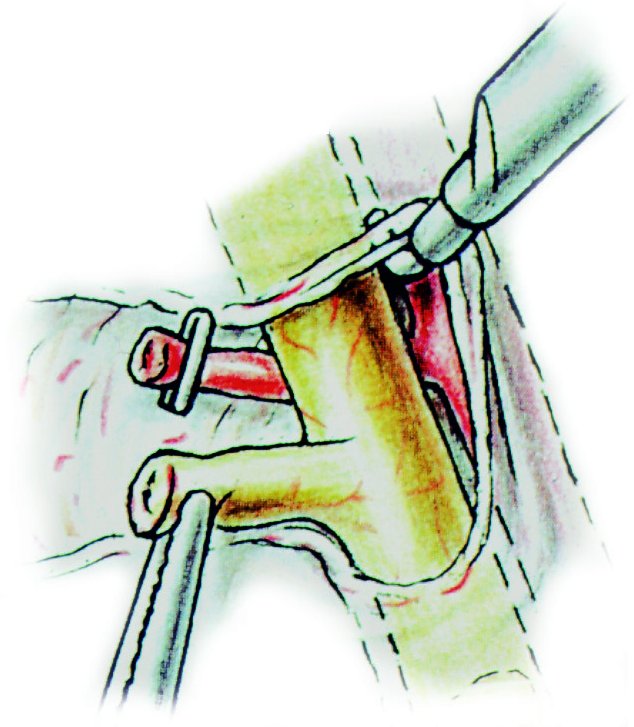

VAGOTOMII TRONCULARE SI SELECTIVE - CHIRURGIE

VAGOTOMII TRONCULARE SI SELECTIVE - CHIRURGIE I. DEFINITIE Vagotomia tronculara reprezinta interventia chirurgicala prin care se rezeca segmentul troncular al nervilor vagi in regiunea esofagiana inferioara, inainte de ramificare (Fig. 1)Citeste tot ... 1792 cuvinte

Dimensiune medie

+ cu poze |